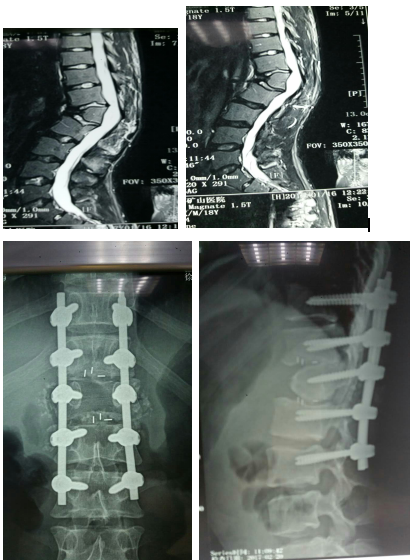

3.先天性椎体发育不良,先天性半椎体会造成脊柱后突畸形,影响患者美观,驼背明显,后背常感疼痛,如畸形明显可能有下肢神经症状,及时采用手术干预,解除脊髓压迫,融合固定,矫正畸形,能取得良好的治疗效果。附典型案例如下: